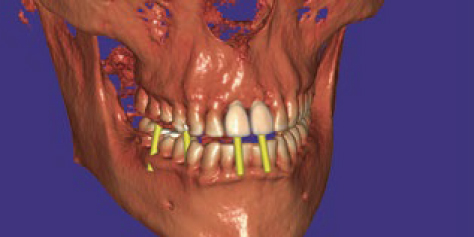

- インプラント設計

インプラント補綴設計

ダイコムビューアー